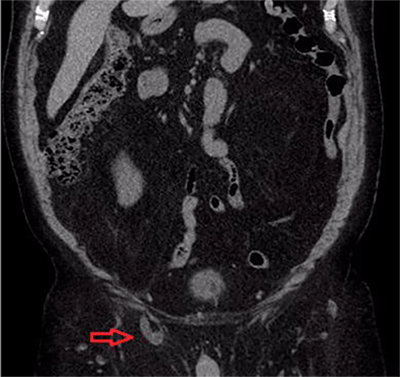

A 67-year-old male with history of hypertension, dyslipidemia, obesity, osteoarthritis, and chronic non-obstructing bilateral nephrolithiasis presented to the emergency department (ED) with a two day history of diffuse abdominal pain. He had associated polydipsia, polyuria and generalized fatigue. The patient reported the presence of chronic inguinal hernias bilaterally, which were asymptomatic and reducible for the last twenty years. During his ED evaluation he denied fever, chills, or changes in bowel habits. He did report hematuria and right sided flank pain with exertion, which he attributed to his known nephrolithiasis. The patient was afebrile and vital signs were within normal limits. Physical examination was remarkable for significant right scrotal swelling consisting of an incarcerated inguinal hernia. In addition, a reducible left inguinal hernia was present. Objective laboratory data included a complete blood cell count and liver function tests, which did not reveal any abnormalities. A renal function panel revealed an increase in the creatinine level to 1.6 mg/dL from his baseline of 0.9 mg/dL that had been constant for the past year. Given his history of nephrolithiasis with acute renal failure, the ED staff along with the medicine team decided to perform a non-contrast computed tomography (CT) to evaluate for acute urinary tract obstruction secondary to stones. The CT scan revealed the following findings: Bilateral fat-containing inguinal hernias, with the right side being larger than the left side, and interestingly, containing the right ureter, which was mildly dilated and extended into the hernia sac (Figure 1). Additionally, retroperitoneal and extraperitoneal fat extended also into the right inguinal hernia (Figure 2). The ureter distal to the sac was decompressed at the level of the internal ring, which raised the concern for incarceration of this portion of the ureter (Figure 3). Finally, the CT also revealed bilateral non-obstructing renal and bladder calculi with significant right sided hydronephrosis that was likely due to the incarcerated ureter (Figure 4).

Figure 3. Coronal view of same study showing dilated incarcerated ureter in hernia sac.